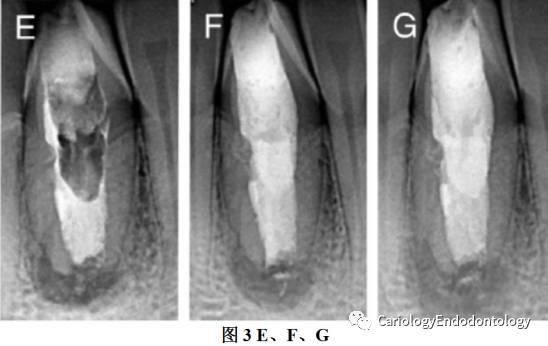

1、根尖区使用MTA完全屏障封闭,X线片显示根尖区MTA封闭大约5mm见图3 E

3、冠方开髓处用临时材料封闭。见图3 F

4、一个月后,患者主诉牙齿唇侧牙龈肿胀。X线片显示根尖区透射区扩大。见图3 G.